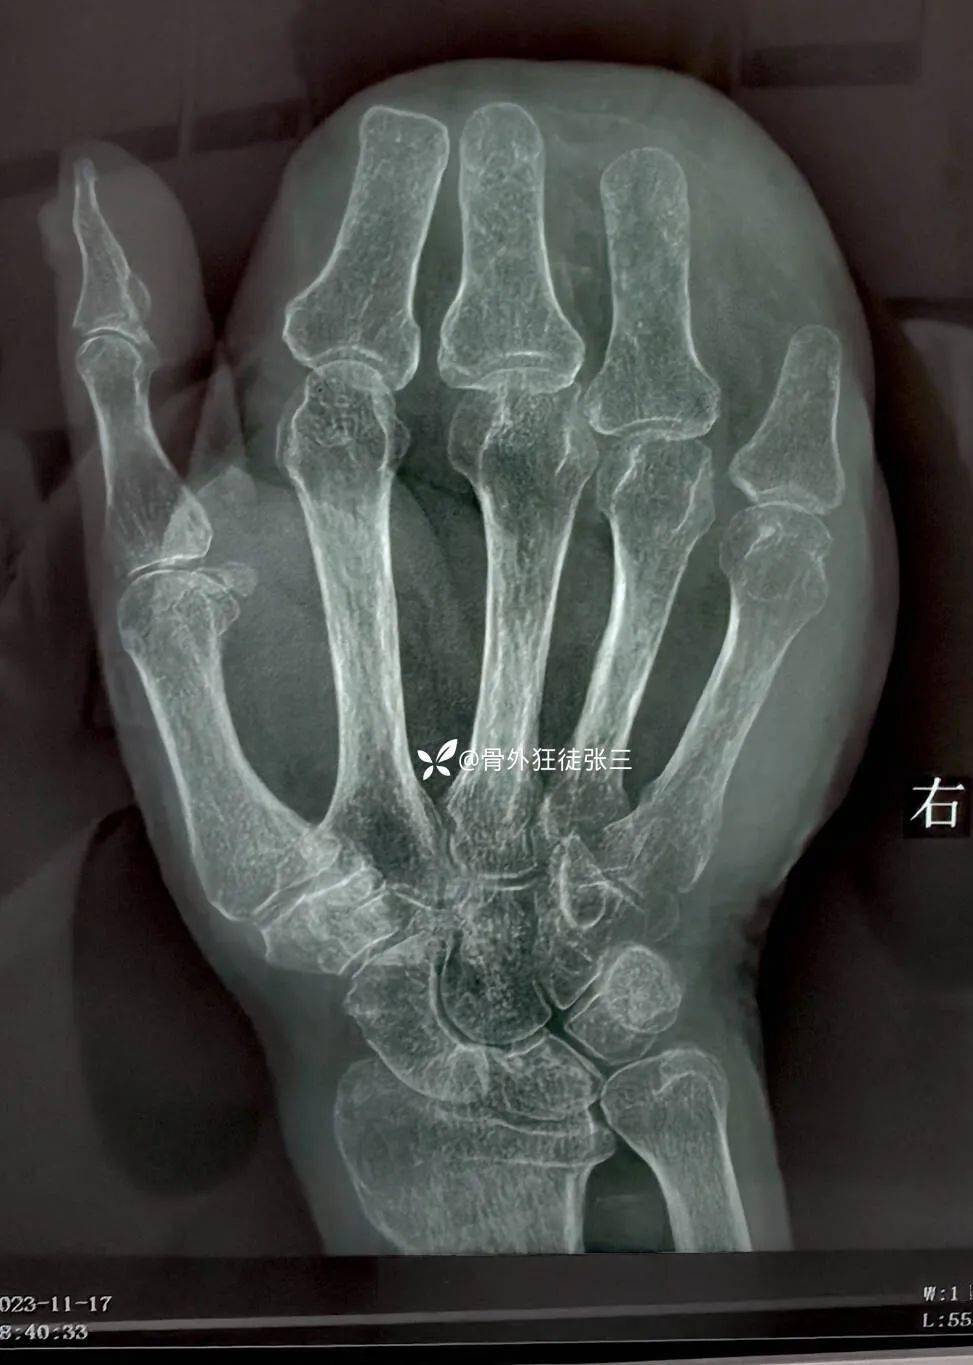

患者情况:男,69 岁。以「右手外伤后皮肤臃肿伴并指畸形 1 年」为主诉来院治疗。

简要病史:1 年前因「右手绞轧性离断伴毁损」,在我院行「游离股前外皮瓣修复创面术」,现患者右手功能尚可,为求分指+皮瓣整形来院。

影像学如下:

目前患者拇对掌功能尚可,能捏持物体。针对上述情况,你认为皮瓣上分指的可行性有多少?分几个指?整形要采用何种方式?抽脂整形?还是传统切开整形?